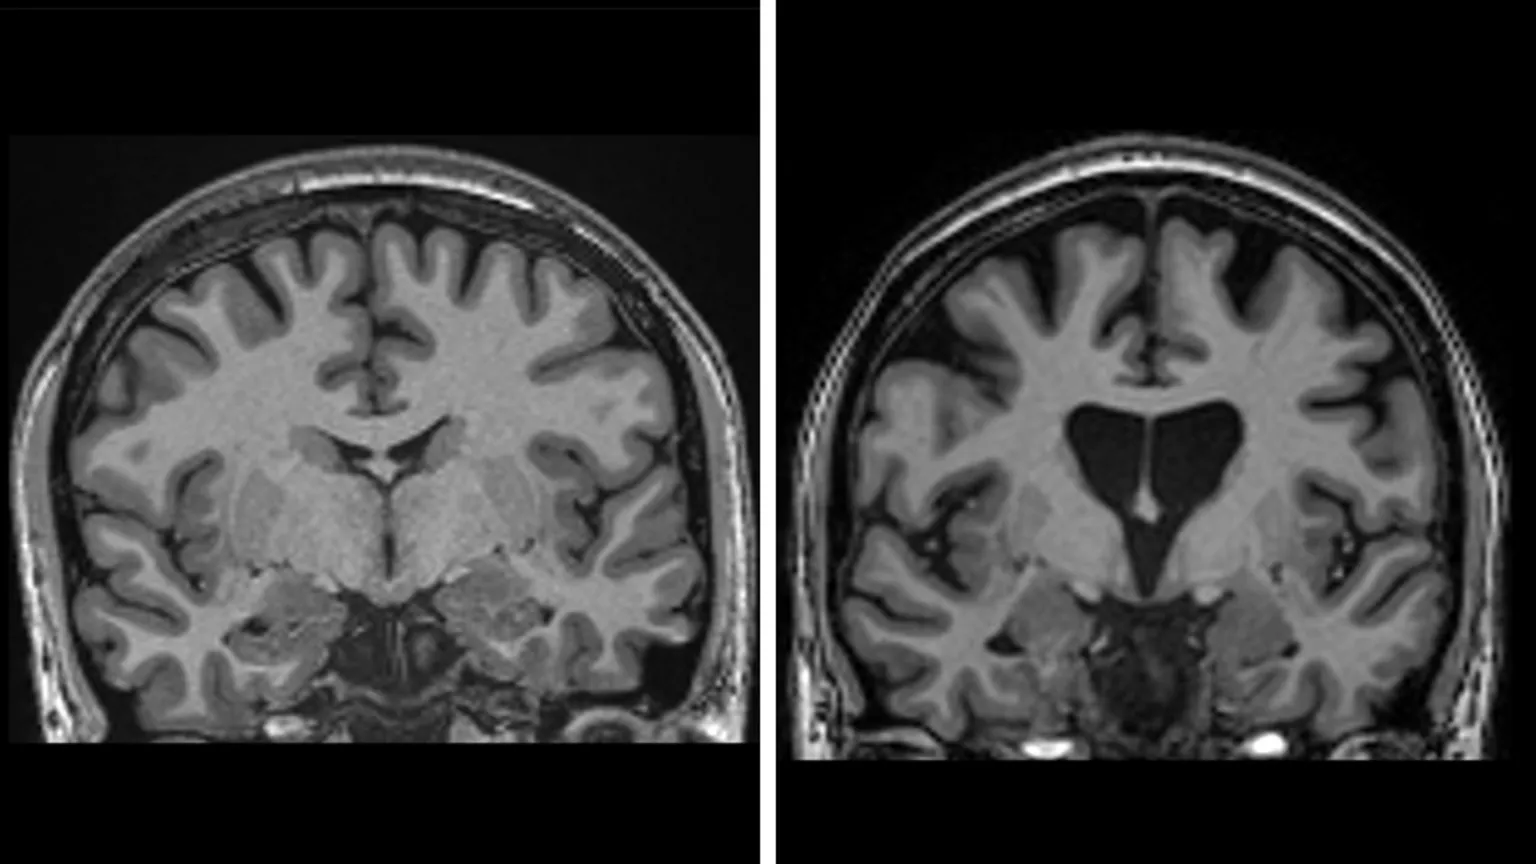

Lo que hace esta enfermedad es degenerar progresivamente las células nerviosas en el cerebro, debido a una mutación genética que convierte la proteína huntingtina en un “asesino de neuronas”, como lo llamaron los expertos.

*Escáner que muestra el antes y después de la enfermedad de Huntington, con pérdida de masa cerebral | Universidad de Carolina del Sur